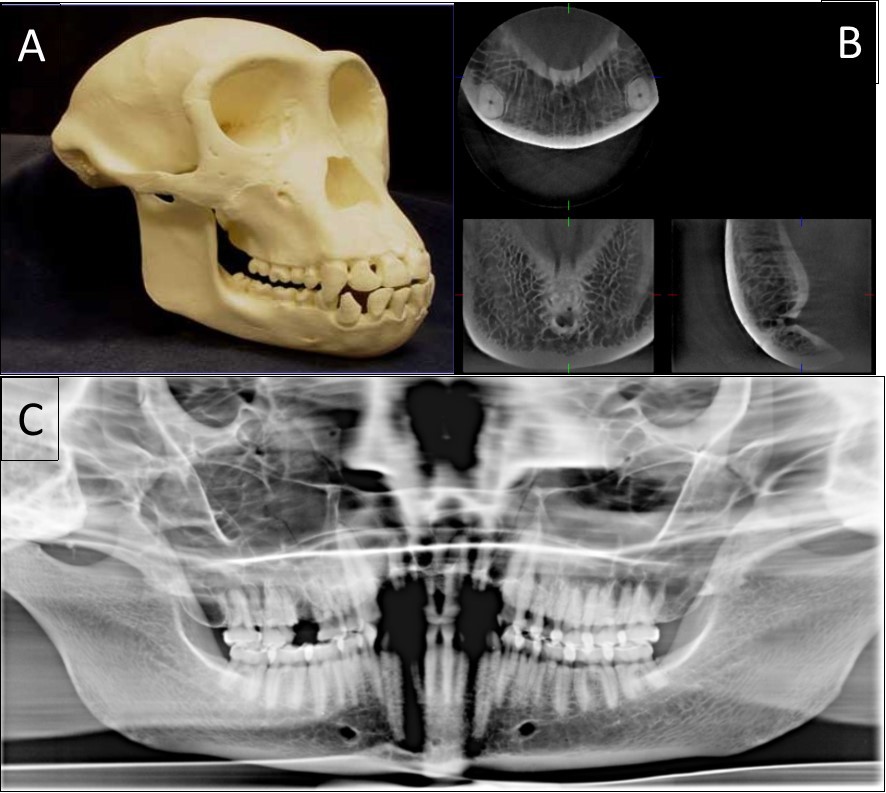

The typical images from modern human and great apes with different anatomical features were shown in Figure 1 and Figure 2. A group of variables were categorized as: the presence of the incisive canal, the number of mandibular canal bifurcations, the potential occurrence of an anterior loop, the presence of the incisive canals, its end-point and connection of the incisive to the lingual canals (Figure 3). Interspecific variability was determined by comparing contemporary human and great ape mandibles. In this analysis, mandibles from the different geographical locations were grouped in the human group, and then compared to mandibles of chimpanzees and gorillas.

Figure 1.The classical sample images with different anatomical features. A general view of a 20-year-old chimpanzee (A), its three-dimensional CBCT view (B) and two-dimensional panoramic view (C).